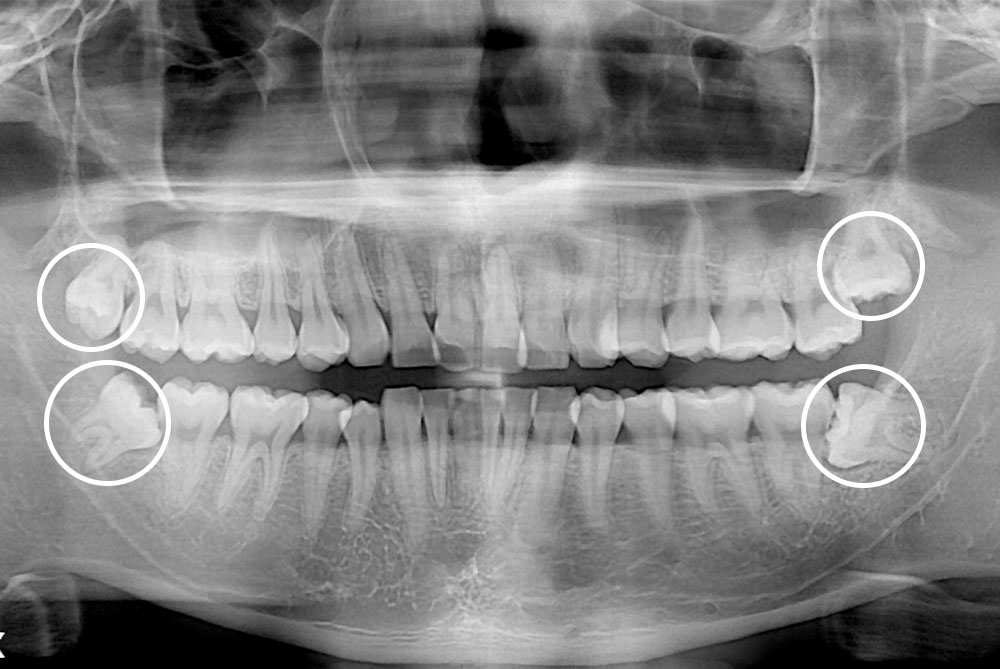

[사랑니] 매복 사랑니 발치

치료후 : 2018-11-22

세종치과는 구강악안면외과학 박사이신 원장님이 발치하는 치과입니다.